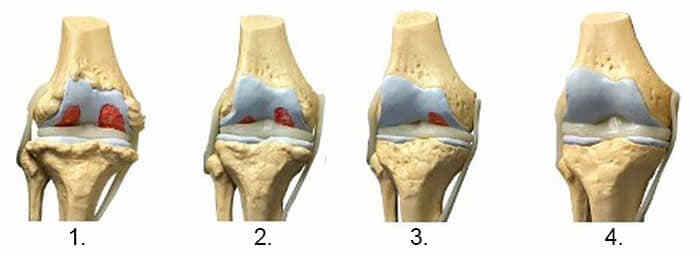

Суглоби

1. Недолік поживних речовин в суглобі. Хрящова тканина руйнується.

2. Відновлення хрящової тканини в суглобі через 2 тижні використання капсул OsteoFix.

3. Відновлення хрящової тканини суглоба через 3 тижні застосування капсул OsteoFix.

4. Здоровий суглоб після одного курсу капсул OsteoFix.